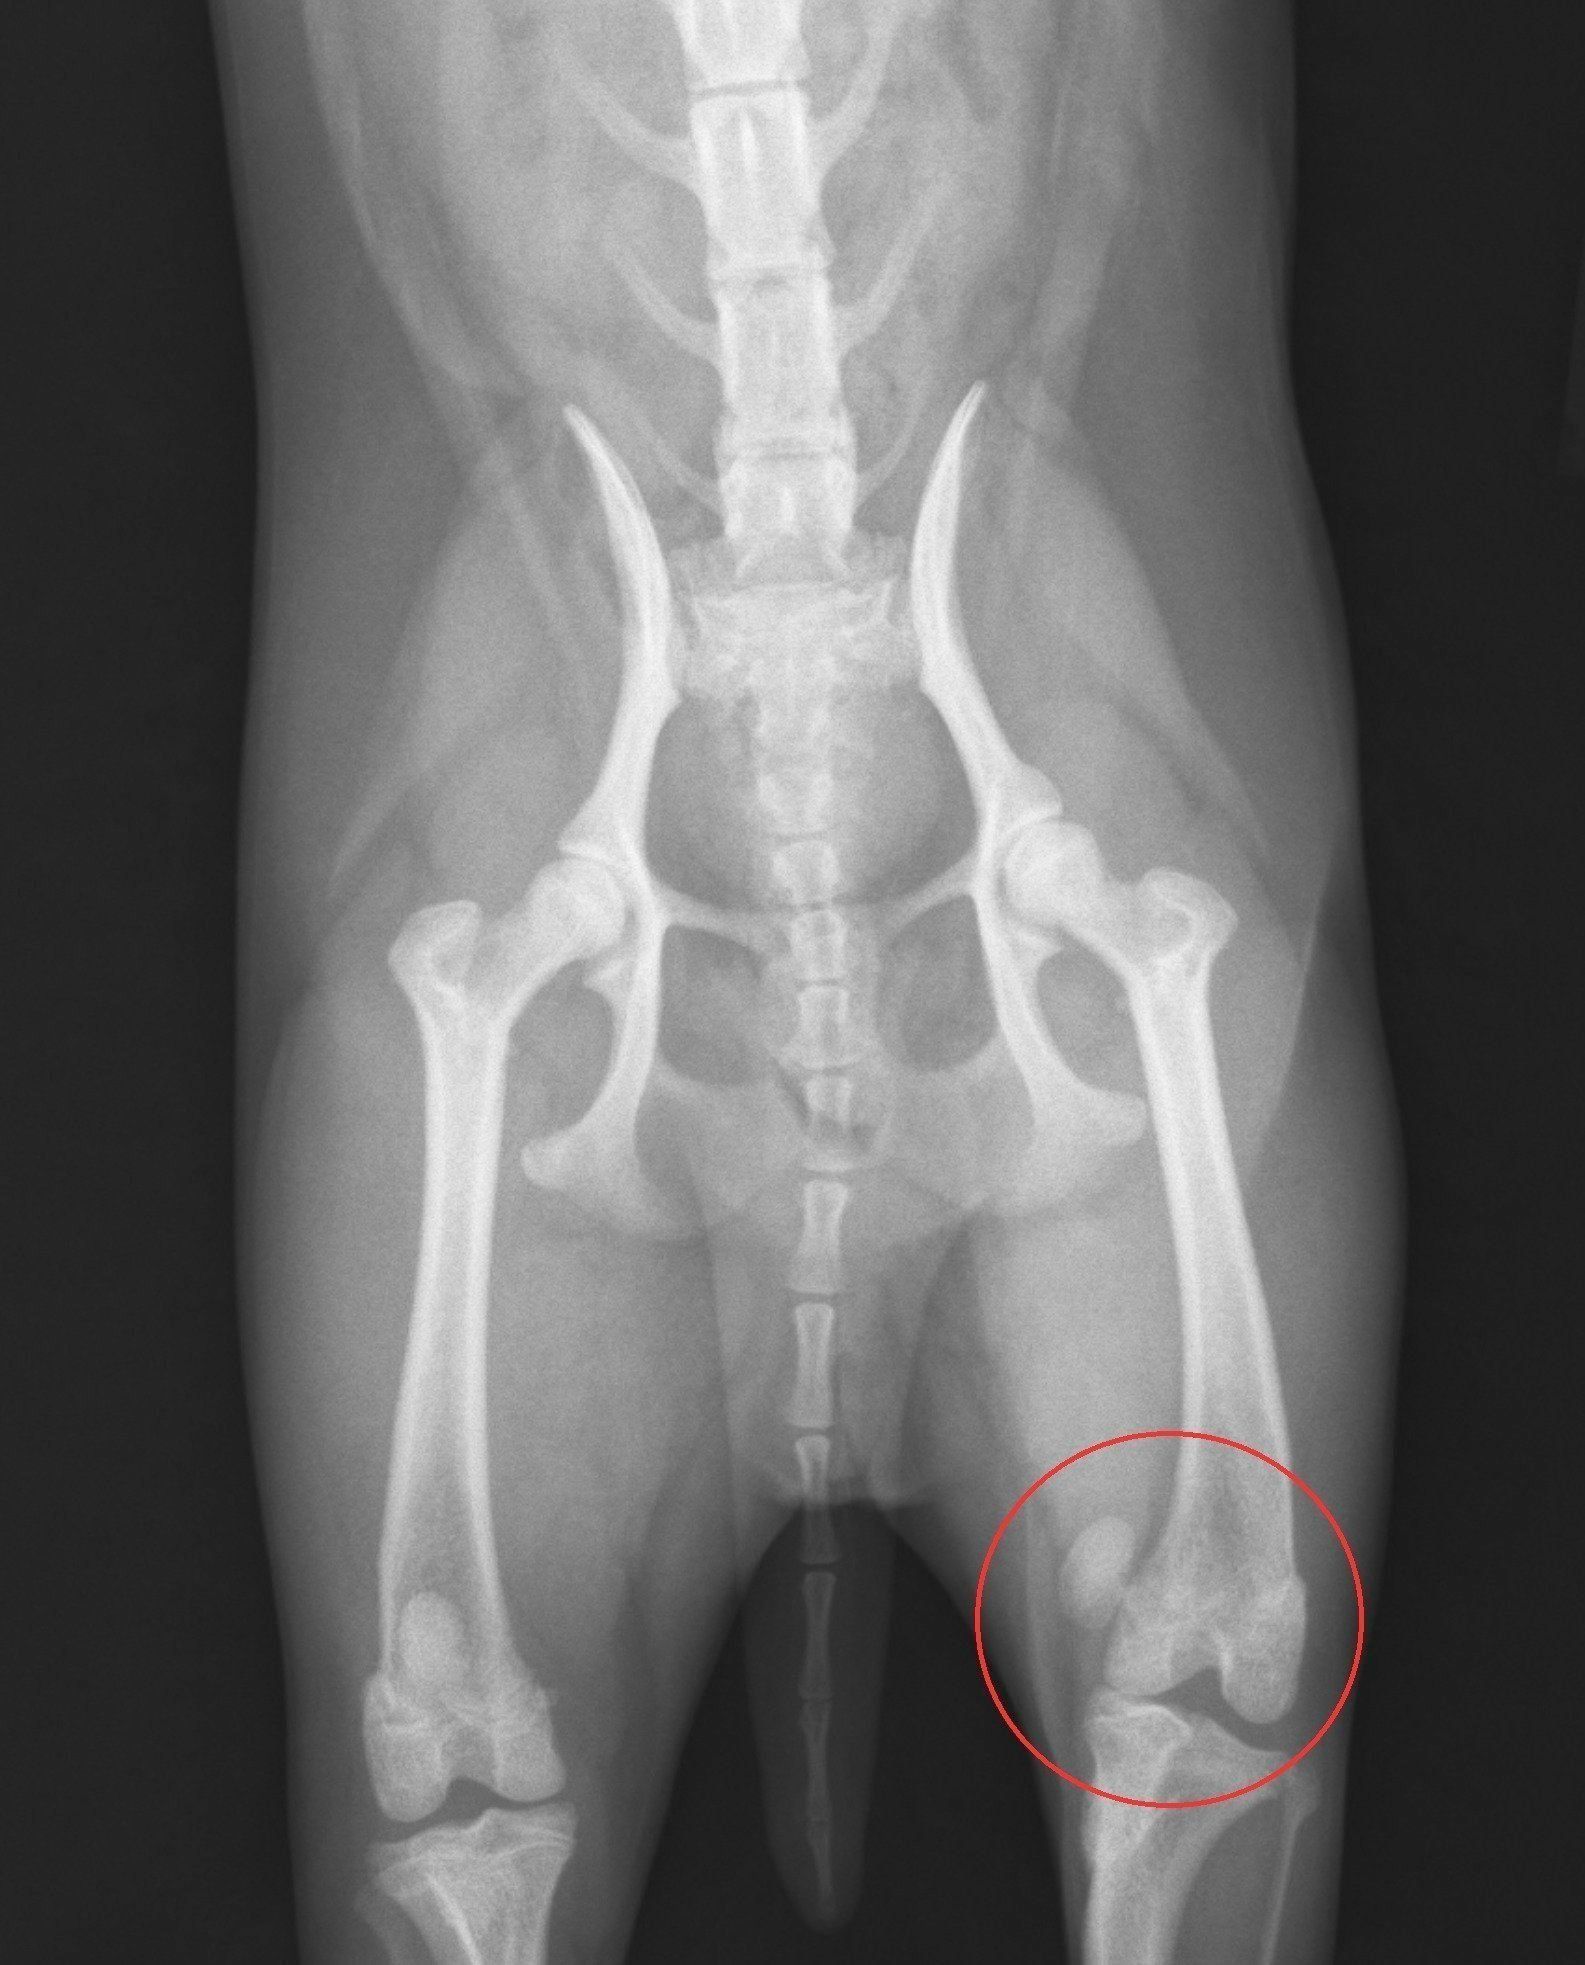

症例写真提供/ノヤ動物病院

左足の膝蓋骨を脱臼している、9カ月のメスのチワワのエックス線写真。画像では右側に見える足で、左上に飛び出している丸い塊が膝蓋骨です。左側の足が正常な状態です。